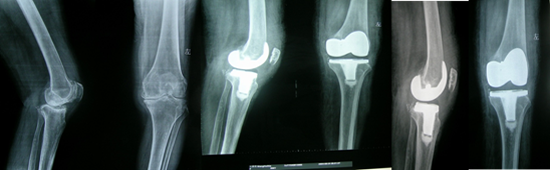

全膝關(guān)節(jié)置換術(shù)